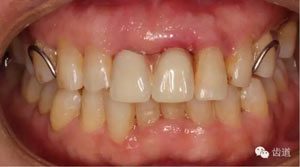

初診照片(正面照)

試戴臨時(shí)活動(dòng)義齒

治療前后對(duì)比

戴牙一年前后對(duì)比